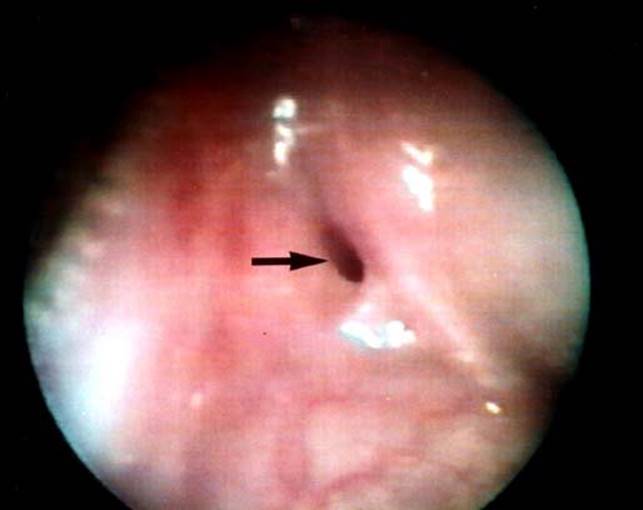

Third and fourth BAs can be grouped together as “pyriform sinus tracts.” Pyriform sinus tracts should be considered in any child with recurrent left neck abscesses or suppurative thyroiditis.8 Direct laryngoscopy with identification of a fistulous opening confirms the diagnosis (Fig. 19.2).

Figure 19.2 Endoscopic localization of a pyriform sinus tract.